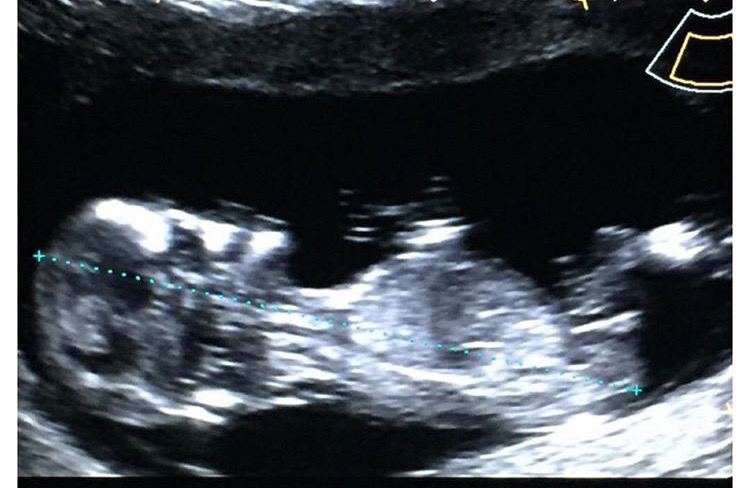

Said I was 12+6 so measuring pretty far aheadAttachment 30517

This is not the nub you are thinking it's actually the baby bent leg and the nub is really the foot so no nub showing

What!? No NUB? Tech seemed to believe the nub was visible, flat and forked.

I guess the tech maybe right but it really looks like a bent leg and the foot to me

I'd be surprised if that's not a nub and I think it looks very girly.x